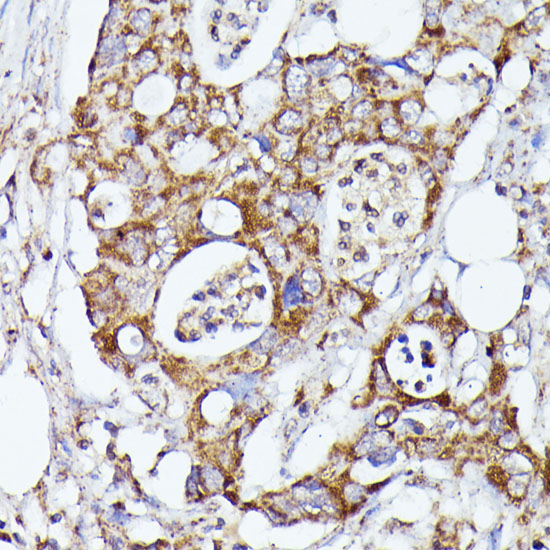

Immunohistochemistry of paraffin-embedded rat liver using CDK5RAP1 antibody.

Immunohistochemistry of paraffin-embedded human colon carcinoma using CDK5RAP1 antibody.

Immunohistochemistry of paraffin-embedded mouse kidney using CDK5RAP1 antibody.